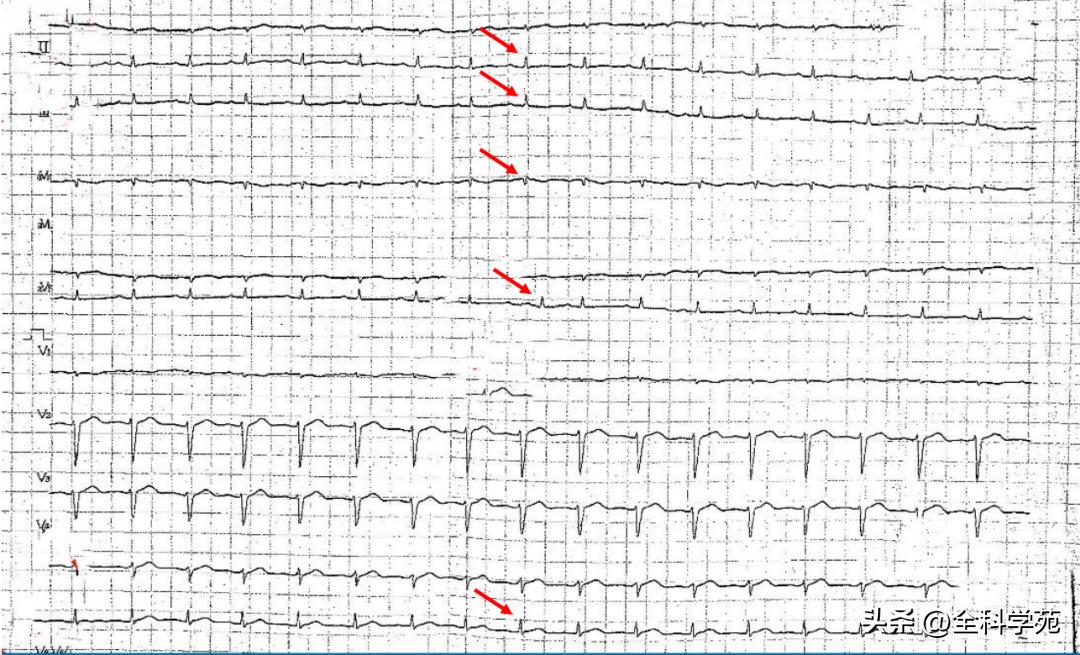

B:心电图示:右束支传导阻滞 , 肢体导联 及 胸前导联低电压ST-T低平

B:心电图示 肢体导联及V5、V6导联低电压 , 广泛ST段抬高

B:心电图:窦性心律不齐,肢体导联低电压

B:心电图: 窦性心律,V2-V6导联T波倒置,肢体导联低电压

3)入院心电图: 全部导联低电压,尤其是肢体导联,同时可见心前区导联电交替